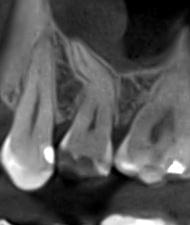

Зуб — це не просто монолітний об'єкт, а складна система мікроканалів. На плоскому 2D-знімку вони часто перекривають один одного, створюючи ілюзію простої анатомії.

Непомічений канал — це джерело майбутньої інфекції та причина «загадкового» болю після лікування. Завдяки високій роздільній здатності обладнання MyRay, лікар бачить кожен мікронний канал ще до того, як візьме до рук інструмент.